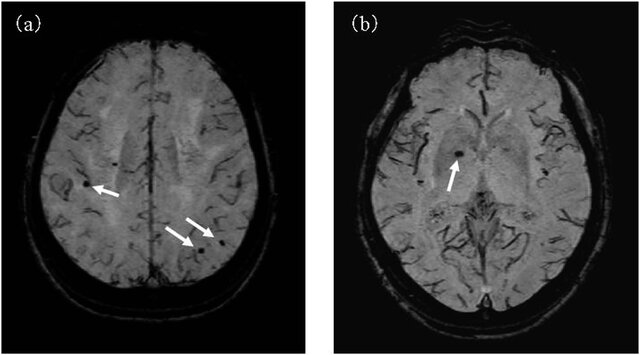

6/ SWI (Susceptibility-Weighted Imaging) β Microbleeds & Hemorrhage

π₯οΈ Detects paramagnetic substances (blood, iron, calcium)

β Microbleeds, Hemosiderin = Dark

β Iron deposition in neurodegeneration = Dark

π Key Uses in Neurosurgery:

β Microhemorrhages (Trauma, CAA, Hypertensive encephalopathy)

β AVMs, Cavernous Malformations

β Hemorrhagic transformation of stroke

β Detection of intra-tumoral hemorrhage

π¨ Best for detecting chronic & microscopic bleeds!

image: DOI: 10.1038/srep38561